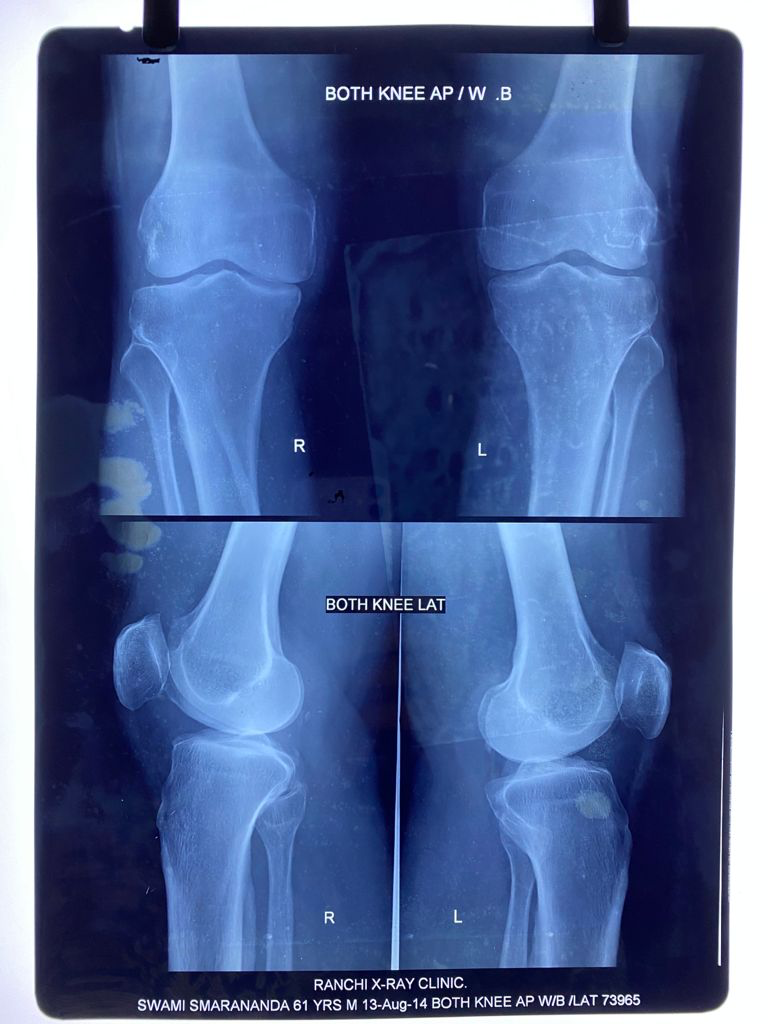

I had an episode of acute knee pain in June 2013. After studying the

X-rays and clinical examination, an Orthopaedic surgeon confirmed the onset

August 13, 2014

August 14, 2014